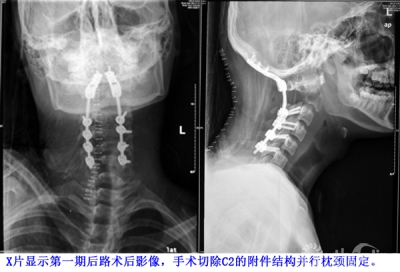

X片显示第一期后路术后影像,手术切除C2的附件结构并行枕颈固定。